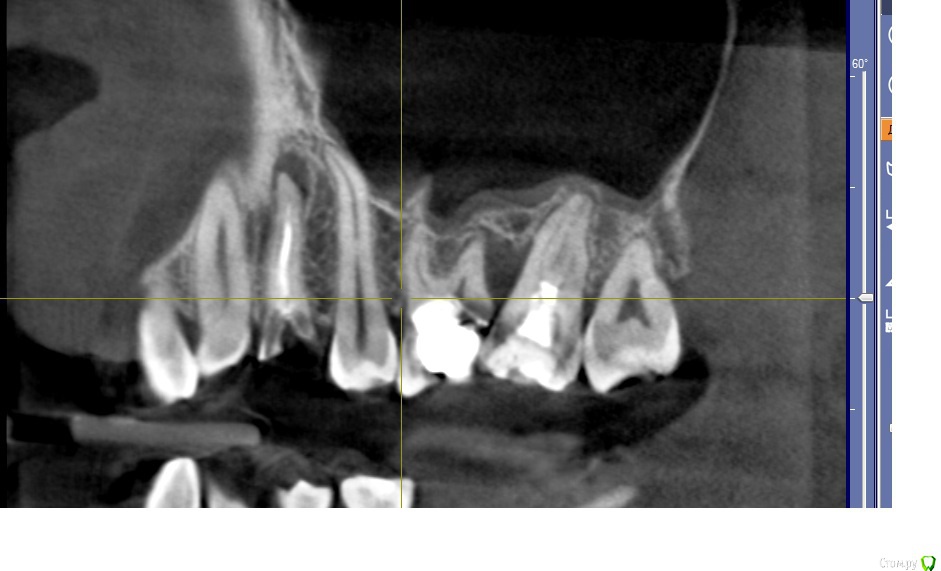

Doctor Vlad Опубликовано 31 января, 2016 Поделиться Опубликовано 31 января, 2016 здравствуйте!зуб 24 и корешок 36 удалены ранее 2 мес назад, слева: и верх и низ молярная группа сохранению не подлежит! 26 ниже уровня кости разрушен... карман между 26 и 27 до верхушки. 7 подвижна слегка. пациент хочет имплант в 24 первоначально. удалять жевательную группу пока не хочет но протезировать будет на имплантах.мои мысли: поставить 24 да пусть он там приживается месяца 3. тем временем удалить верх 26 27 кюретаж засыпать БИООС для сохранения высоты кости мембрана зашить. 28 как стенка дефекта пусть постоит) по заживлению верха удаление низ 37 38. через 3 месяца импланты в области 26 и 36.. чз месяца 3 одновременно запротезировать 24 26 36 и ввести в функцию.не стоит отдельно перегружать 24, лучше уговорить на одномоментную нагрузку? сильно перегрузиться правая сторона за время отсутствия левой? ваше мнение? альтернативные варианты.. предложения)? Ссылка на комментарий